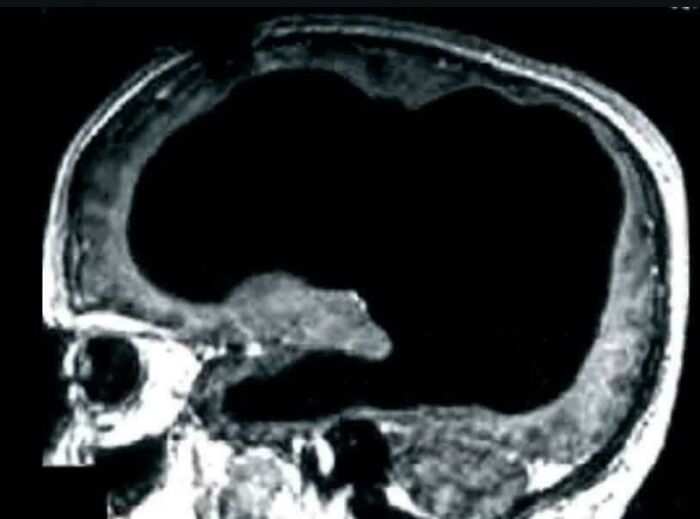

A man was discovered to be unknowingly missing 90% of his brain yet he was living a normal life. The man's skull was full of liquid, with just a thin layer of brain tissue left. The condition is known as hydrocephalus. His IQ was only very slightly below the normal range.